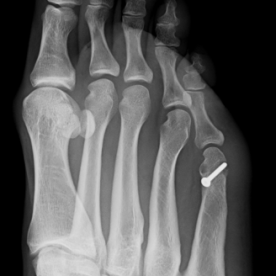

11) Hallux rigidus

Arthrose des Großzehengrundgelenkes. Im Frühstadium erfolgt eine konservative Therapie, im fortgeschrittenen Stadium ist eher eine operative Therapie angezeigt. Sie umfasst die Abtragung von Knochenausziehungen, ggf. ist eine prothetische Versorgung oder eine Versteifung des Großzehengrundgelenkes notwendig.

Röntgenbilder